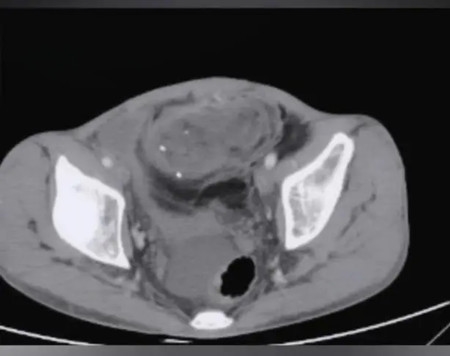

外观上看,肿瘤已经占据了患者整个腹盆腔,患者增强CT结果更是不容乐观,腹盆腔可见巨大混杂密度影,病灶多发、融合态,大小约25×15×25cm,动脉期可见多发血管进入,与肾脏、输尿管、胆囊、肝脏、十二指肠等紧密相连,腹盆腔脏器受压移位,小肠、结肠被挤压至腹腔一角,脾静脉与肾静脉局部狭窄,最大病灶向后方压迫下腔静脉和腹主动脉,同时可见病灶经左侧腹股沟入左侧阴囊。

▲ 患者术前检查影像